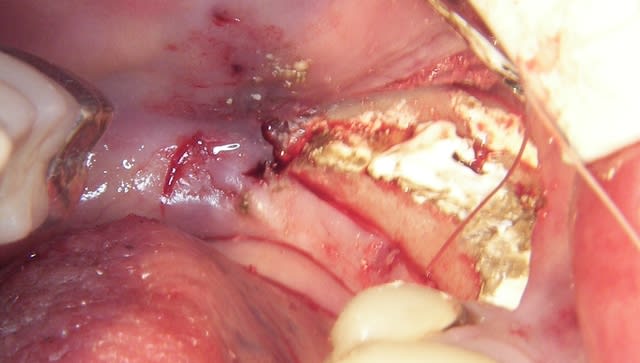

L’incision est décalée par rapport à la crête, en vestibulaire, car je ne veux pas décoller le périoste sur la partie osseuse qui est mobilisée.

Je pense que ça permet de "nourrir" le "greffon" et surtout si la table interne venait à se rompre le "greffon" ne serait que semi-mobile.

J’ai donc fait une expansion verticale et latérale puisque je n’ai pas coupé la corticale linguale, du moins dans sa partie postérieure, et j’espère gagner sur les deux tableaux, mais il était risqué de mettre en plus les implants.

quelques photos en "grand"

--

Il y a deux incisions séparées de 1,5 à 2mm, initiées au disque (double comme sur les motos) et finies au piézo

Il est illusoire de croire que l'os mandibulaire se laisse "pénétrer" simplement.

Et surtout il faut pouvoir retirer le distracteur ensuite.